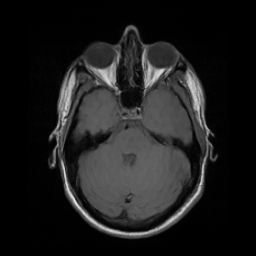

Motion artifacts are a primary source of magnetic resonance (MR) image quality deterioration with strong repercussions on diagnostic performance. Currently, MR motion correction is carried out either prospectively, with the help of motion tracking systems, or retrospectively by mainly utilizing computationally expensive iterative algorithms. In this paper, we utilize a novel adversarial framework, titled MedGAN, for the joint retrospective correction of rigid and non-rigid motion artifacts in different body regions and without the need for a reference image. MedGAN utilizes a unique combination of non-adversarial losses and a novel generator architecture to capture the textures and fine-detailed structures of the desired artifacts-free MR images. Quantitative and qualitative comparisons with other adversarial techniques have illustrated the proposed model's superior performance.

翻译:移动文物是磁共振(MR)图像质量恶化的一个主要来源,对诊断性能产生强烈影响。目前,MR运动的校正要么是预期性的,借助运动跟踪系统,要么是追溯性的,主要是利用成本昂贵的计算迭代算法。在本文中,我们使用名为MedGAN的新颖的对抗性框架,联合追溯性地校正不同身体区域的硬性和非硬性运动文物,而不需要参考图像。 MedGAN利用非对抗性损失和新型生成器结构的独特组合来捕捉无MR图象的纹理和精细详细结构。 与其他对抗性技术的定量和定性比较展示了拟议模型的优异性表现。